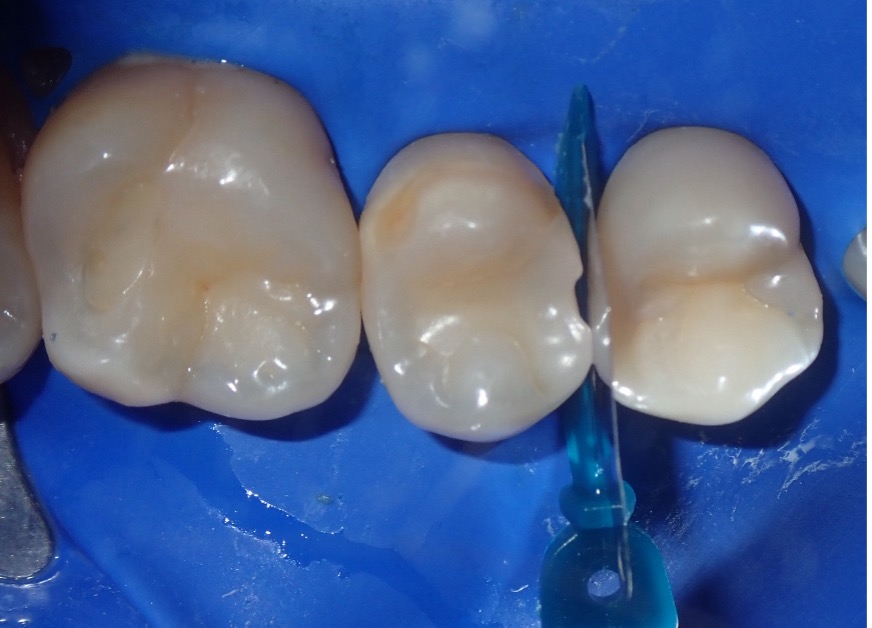

The final restorations demonstrated tight, anatomically correct proximal contacts, ensuring proper tooth alignment and function. They also exhibited excellent marginal adaptation and a high-quality polish, contributing to both durability and esthetics. Additionally, the restorations maintained functional occlusion, resulting in high patient satisfaction with both comfort and appearance (Fig. 12).

Figure 12

Figure 12. Restorations exhibit tight proximal contacts, smooth surfaces, and natural anatomy, ensuring function and esthetics.